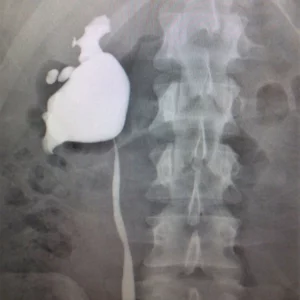

The kidneys’ job is to filter your blood. They remove wastes, control the body’s fluid balance, and keep the right levels of electrolytes. All of the blood in your body passes through them several times a day. Blood comes into the kidney, waste gets removed, and salt, water, and minerals are adjusted, if needed. The filtered blood goes back into the body. Waste gets turned into urine, which collects in the kidney’s pelvis — a funnel-shaped structure that drains down a tube called the ureter to the bladder.Each kidney has around a million tiny filters called nephrons. You could have only 10% of your kidneys working, and you may not notice any symptoms or problems. If blood stops flowing into a kidney, part or all of it could die. That can lead to kidney failure.